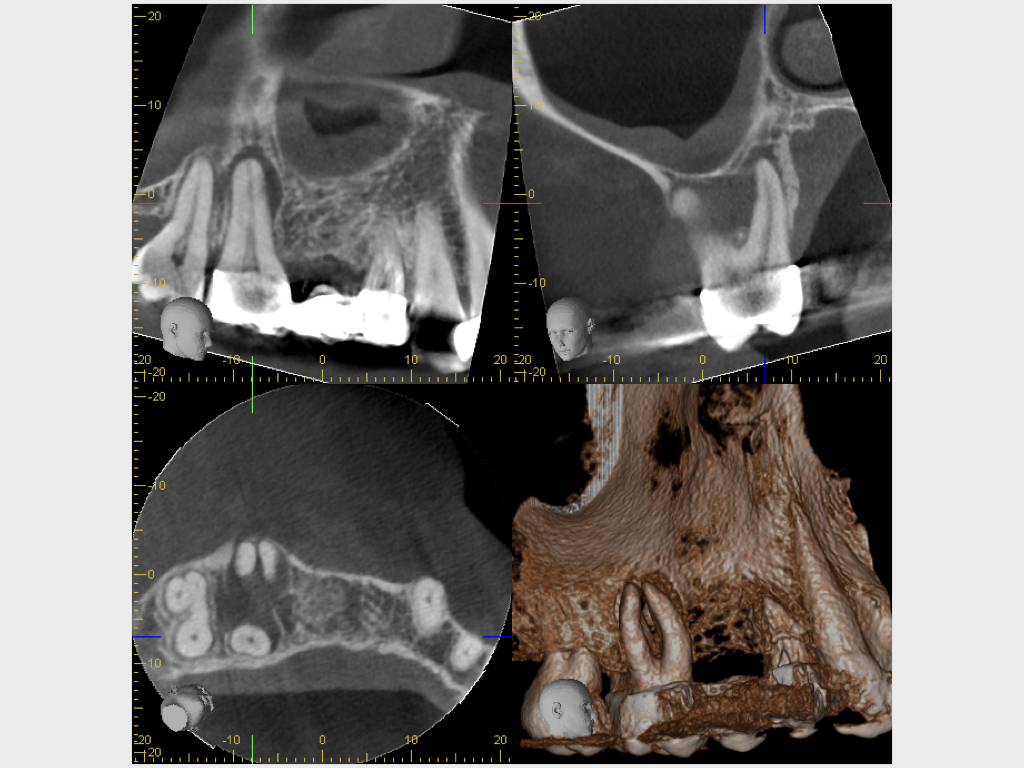

Heilung Express oder Radiodontics